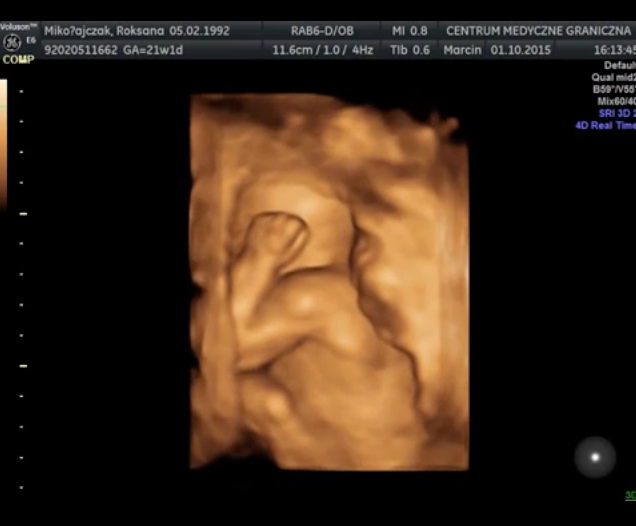

Wyniki badań prenatalnych są bardzo dobre. Obecnie trwa 23 tydzień ciąży, a mała waży 500 gram. Lekarz zalecił mi jednak kontrolę przepływu krwi, ponieważ obecne wyniki mieszczą się w górnej granicy normy 101cm/s. Wykonanie USG nie było wcale takie proste – maleńka Kasia jest bardzo ruchliwa i nie pozwalała się zmierzyć podczas badania. W czasie jego trwania udało się nagrać kilka krótkich filmów i zdjęć, możecie je zobaczyć poniżej. Kolejne badanie prenatalne odbędzie się 10-go grudnia. Termin porodu wyznaczono na 11 lutego i prawdopodobnie odbędzie się za pomocą cesarskiego cięcia.